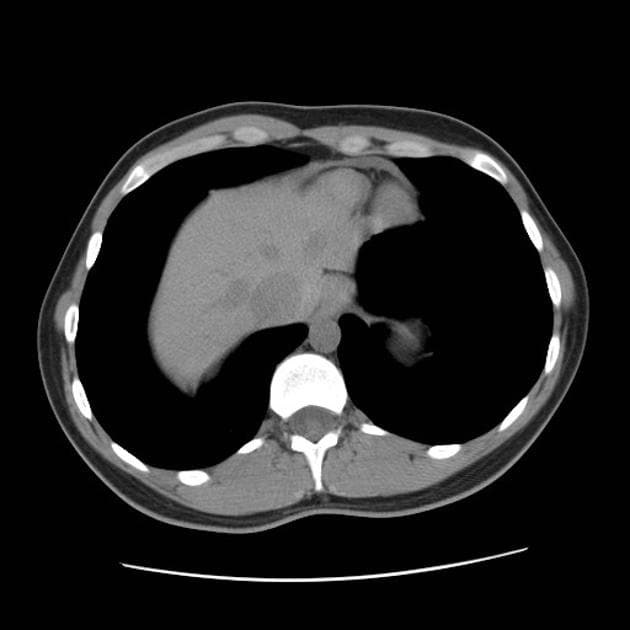

Axial renal excretory phase

Đã biết hội chứng Von Hippel-Lindau (VHL). Đang sàng lọc các khối u thận. Bệnh nhân có bàng quang thần kinh. Chụp cộng hưởng từ (MRI) được thực hiện nhằm giảm phơi nhiễm tia phóng xạ.

- Nhiều nang thận đơn thuần cũng như nhiều u thận tổn thương hỗn hợp đặc - nang.

- Tuyến tụy cũng chứa một số lượng rất lớn các nang rải rác khắp nơi.

Ca lâm sàng này biểu hiện đầy đủ các đặc điểm của hội chứng Von Hippel-Lindau (VHL), bao gồm nhiều nang thận đơn thuần và nhiều u thận tổn thương hỗn hợp đặc - nang. Tuyến tụy cũng có rất nhiều nang lan tỏa.

Bệnh nhân đã từng được phẫu thuật cắt bỏ u mạch thần kinh đệm (hemangioblastoma) ở tủy sống, gây ra tình trạng bàng quang thần kinh (lưu ý hình ảnh cắt lớp ngang T2 cho thấy dấu hiệu của phẫu thuật cắt mảnh cung (laminectomy) vùng ngực và các thay đổi tại tủy sống).